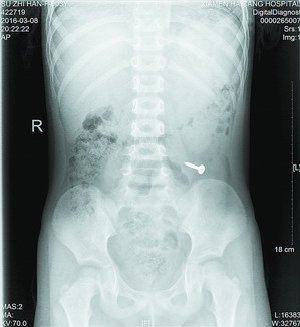

值班的叶医生了解情况后,马上安排女孩做X光片检查,检查影像一出来,大家都吓了一跳,只见女孩左下腹位置清晰地躺着一个金属异物,经再三辨认,确定是一颗螺丝钉。叶医生马上安排女孩转诊小儿外科治疗。儿外科医生接诊后,考虑患者年龄太小,手术损伤大,且目前没有腹痛、腹膜炎等肠穿孔征象,螺丝钉有可能自行排出,便建议随访,叮嘱女孩多吃些富含纤维素的食物,加速螺丝钉的排出。同时告知女孩家长密切观察孩子的身体情况。昨日,女孩再来海沧金沙集团 拍片复查,发现螺丝钉已经顺利排出了。